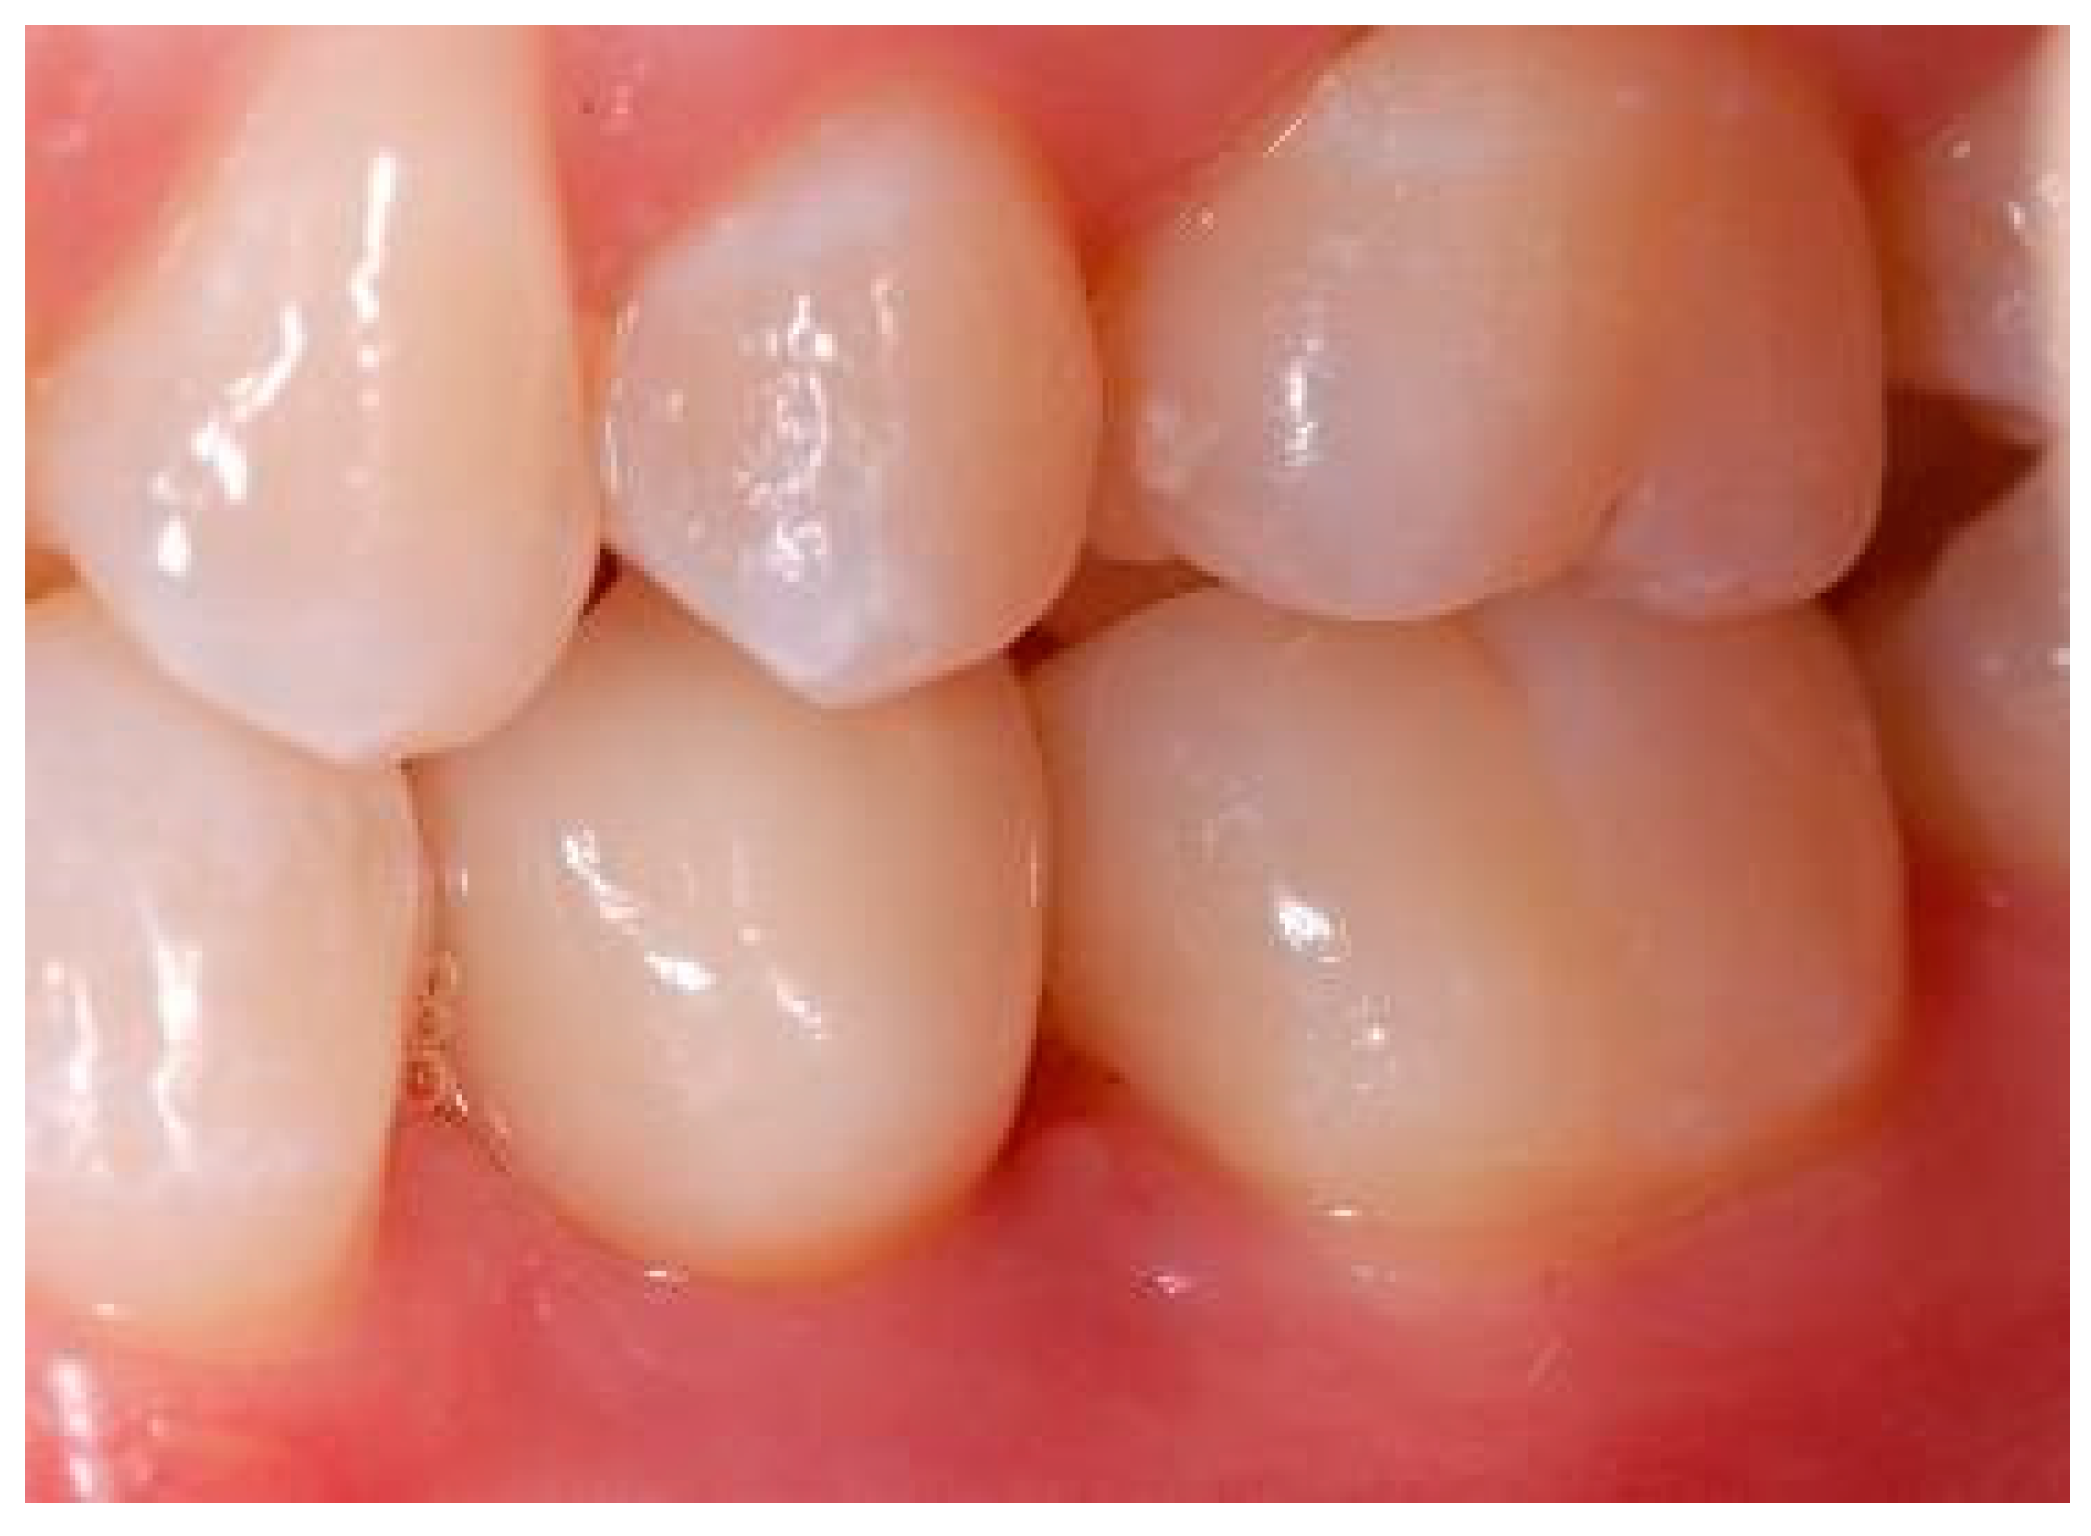

Appendix A. Exemplary Photographs and Radiographs from a Patient at Different Examination Time Points and a Positive Outcome